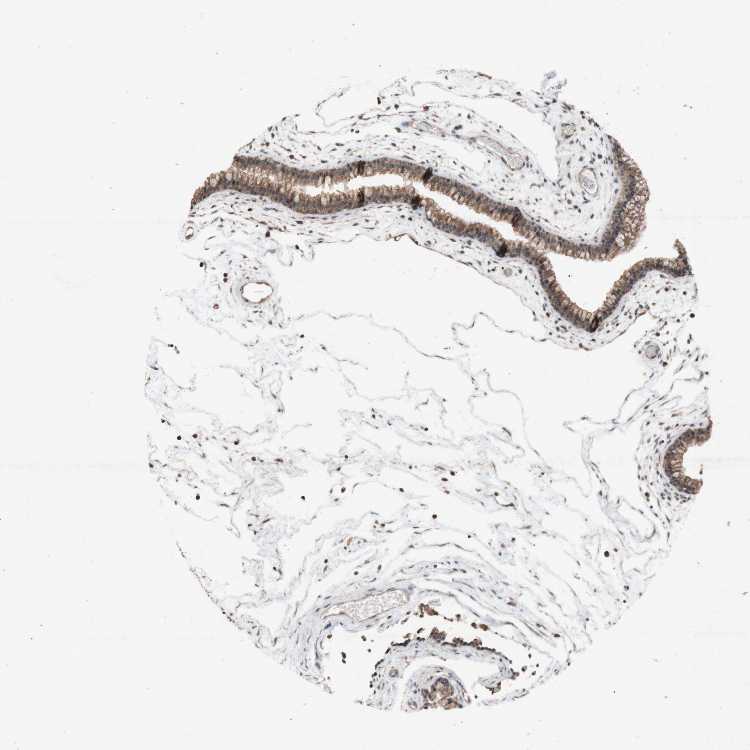

TISSUE PRIMARY DATA NASOPHARYNX Show tissue menu

NASOPHARYNX - Antibody stainingi

Antibody staining in the annotated cell types in the current human tissue is reported as not detected, low, medium, or high, based on conventional immunohistochemistry profiling in selected tissues. This score is based on the combination of the staining intensity and fraction of stained cells.

Each image is clickable and will lead to virtual microscopy that enables deeper exploration of all samples and also displays staining intensity scores, fraction scores and subcellular localization as well as patient and tissue information for each sample.

Antibody HPA048700Antibody HPA062011Antibody CAB009529

Respiratory epithelial cells MediumMediumMedium